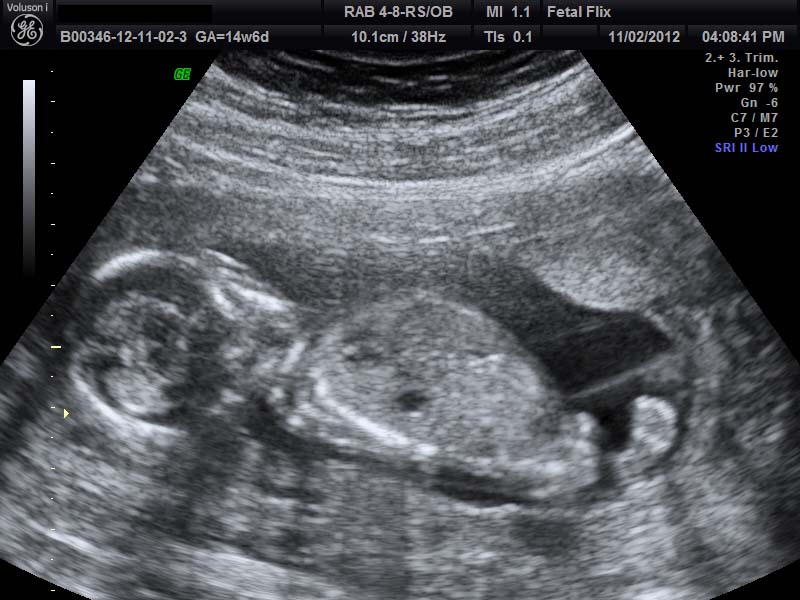

I would told boy, but baby only measured 14w2d. Any thoughts???

boy its early but nub and potty shots 100% boy

Yeah, looks like something is sticking out in the first pic and second picture looks like a boy nub. :)

Not sure to be honest, the potty shot reminds me of girl bits protruding which the would at this age, and the nub shot, I don't see one

This is my 14 w 6 day boy shot....mine looks a lot different than yours!